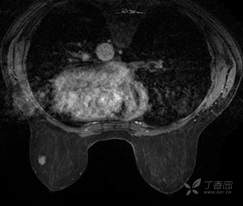

乳腺动态增强MRI 对比剂(钆布醇)

T2WI脂肪抑制序列

T1WI平扫脂肪抑制序列

DWI

T1WI增强早期

T1WI增强晚期

乳腺MR:左乳外上象限见T2WI高信号肿块影,大小约12mm×10mm×13mm,肿块为卵圆形,边缘模糊不规则;内部强化略不均匀;TIC曲线初始相呈快速强化,延迟期呈平台型;DWI呈高信号,ADC值为 0.000698 mm2/s。

因肿块边缘不规则,内部强化不均匀, TIC曲线初始相呈快速强化,延迟期呈平台型;DWI呈高信号,ADC值较低,考虑左乳外上象限肿块恶性不除外,BIRADS 4类。